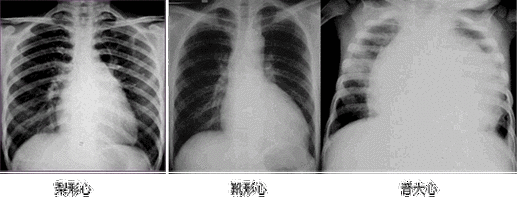

临床执业医师实践技能考试心脏增大诊断公式